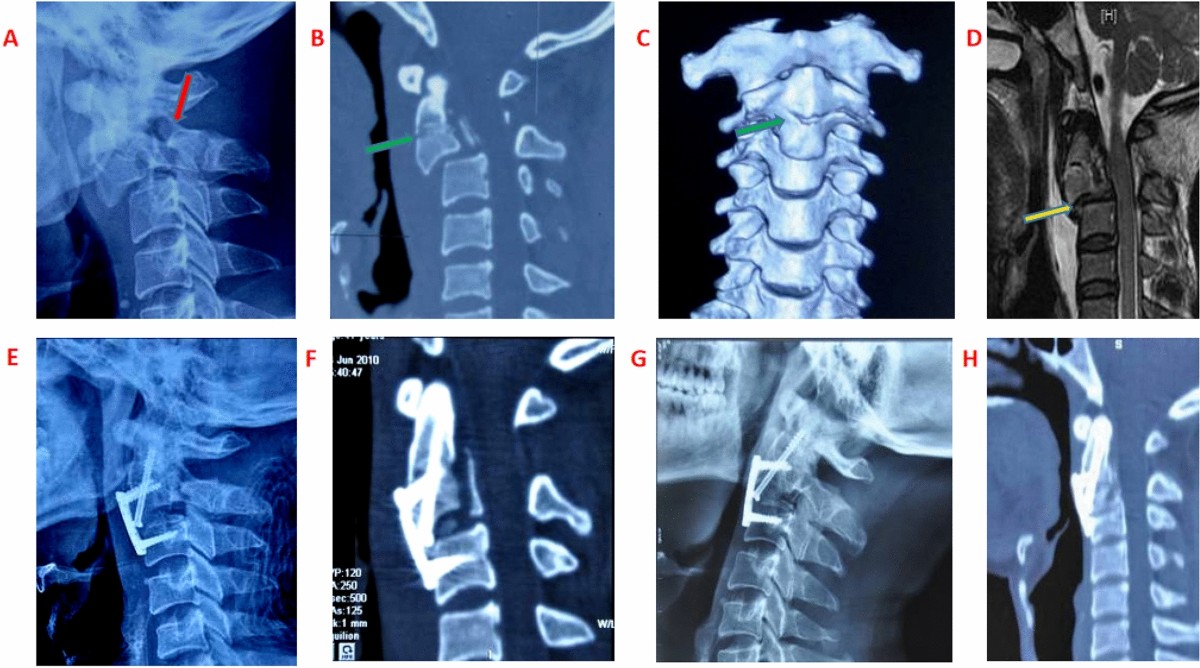

Surgical Management of Hangman's Fracture: A Systematic Review |  International Journal of Spine Surgery, image size:1692x1800

Surgical Management of Hangman's Fracture: A Systematic Review | International Journal of Spine Surgery